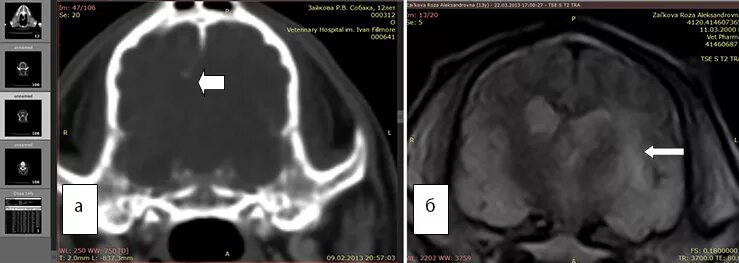

Перифокальный отек образования